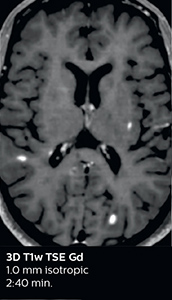

A two year follow-up scan of a CPA meningioma using both Ingenia 3.0T without CS and Ingenia Elition 3.0T with Compressed SENSE allows for a nice comparison to demonstrate the protocol improvements achieved on the Elition: 3D FLAIR has a shortened scan time, improved SNR and still the same spatial resolution. BrainView (3D T1 TSE) has improved spatial resolution and SNR with shortened scan time. For 3D T2 Drive the spatial resolution has been improved. 3D THRIVE used to have an interpolated 0.8 mm slice thickness, but true thickness at 1.6 mm, so that axial slices displayed a decent quality, but reformats were suboptimal. Compressed SENSE is used on Elition to improve spatial resolution and reduce the non-interpolated slice thickness to allow smoothly reformatted images. Total scan time (adding SmartBrain and an additional b2000 diffusion) was 13:19 on Ingenia, and is now reduced to 10:42 on Ingenia Elition.

Ingenia 3.0T (without Compressed SENSE)

3D FLAIR 1.0 x 1.0 x 1.0 mm* 4:24 min.

3D TSE T1w 1.0 x 1.0 x 1.2 mm* 2:40 min.

3D T2w Drive 0.8 x 0.8 x 1.0 mm* 3:05 min.

3D T1w THRIVE 0.8 x 0.8 x 1.6 mm* 1:30 min.

Ingenia Elition 3.0T with Compressed SENSE

3D FLAIR 1.0 x 1.0 x 1.0 mm* 2:50 min.

3D TSE T1w 1.0 x 1.0 x 1.0 mm* 2:10 min.

3D T2w Drive 0.7 x 0.7 x 0.7 mm* 2:52 min.

3D T1w THRIVE 0.7 x 0.7 x 0.8 mm* 1:30 min.

*true voxel size, without interpolation